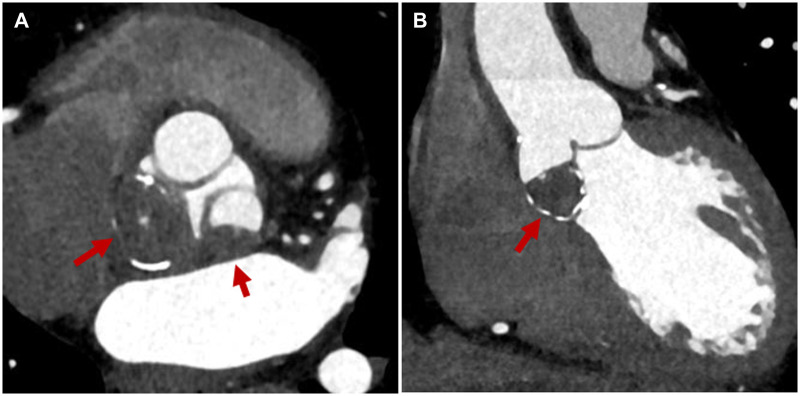

主动脉瓣周围的肿瘤或肿瘤样病变相对罕见且难以诊断。我们报告一个有趣的病例钙化血栓在Valsalva窦和冠状动脉尖,模仿主动脉瓣肿瘤。68岁男性,经超声心动图和增强计算机断层扫描发现,非冠状动脉和左冠状动脉尖部有20毫米钙化肿块,延伸至相应的Valsalva窦。切除病变以确定诊断并防止全身栓塞。术中及组织病理学检查显示非冠状动脉小叶萎缩,Valsalva鼻窦及鼻尖邻近部分动脉粥样硬化灶钙化,伴有溃疡和纤维蛋白血栓。切除病变并行主动脉瓣置换术以避免主动脉瓣功能障碍。患者房颤得到控制,术后3个月停用抗凝药物。手术来确定诊断和预防系统性血栓栓塞被认为是合理的,即使在没有瓣膜功能障碍的情况下。

Tumours or tumour-like lesions around the aortic valve are relatively rare and are difficult to diagnose. We report an interesting case of calcified thrombi in the Valsalva sinuses and coronary cusps that mimicked an aortic valve tumour. A 68-year-old man presented with a 20-mm calcified mass in the non-coronary and left-coronary cusps extending to their corresponding Valsalva sinuses, which was detected by echocardiography and contrast-enhanced computed tomography. The lesions were resected to establish the diagnosis and prevent systemic embolization. Intraoperative and histopathological examination revealed an atrophied non-coronary leaflet and calcified atherosclerotic lesions of the Valsalva sinuses and contiguous parts of the cusps, with ulceration and fibrin thrombi. The lesions were resected and aortic valve replacement was performed to avoid aortic valve dysfunction. The patient's atrial fibrillation was controlled, and anticoagulants were discontinued 3 months postoperatively. Surgery to establish the diagnosis and to prevent systemic thromboembolism was thought to be reasonable, even in the absence of valvular dysfunction.